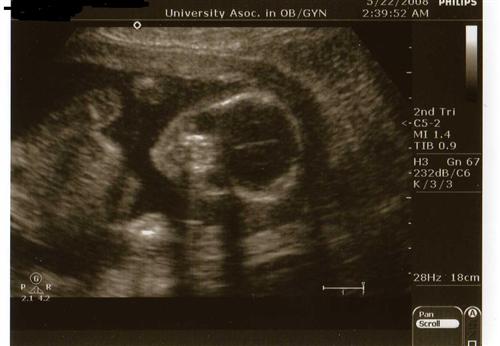

Re: Baby Neener update w/PICS

Oh wow just saw your sono pix!!! SO FANTASTIC!!!!! Hey is it just my imagination, or is this little baby smiling right at you???

Yep, I saw the smile too!!!!!!